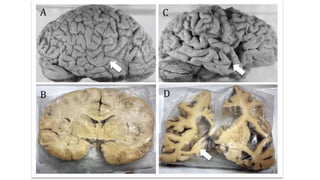

• O hipocampo é uma

estrutura alongada que se

situa no lobo temporal

medial.

• Na frente dele está a

amígdala, cuja posição é

mostrada no corte B.

• Na figura em A, amígdala e

hipocampo estão

mostrados projetados na

superfície lateral do

encéfalo, mas na verdade

posicionam-se na face

• Um corte menos inclinado

(C) permite - com maior

ampliação (D) - visualizar as

regiões vizinhas e

funcionalmente

relacionadas ao

hipocampo.

• O hipocampoé uma estrutura alongada que se situa no lobo temporal medial. • Na frente dele está a amígdala, cuja posição é mostrada no corte B. • Na figura em A, amígdala e hipocampo estão mostrados projetados na superfície lateral do encéfalo, mas na verdade posicionam-se na face medial. • Um corte menos inclinado (C) permite - com maior ampliação (D) - visualizar as regiões vizinhas e funcionalmente relacionadas ao hipocampo.